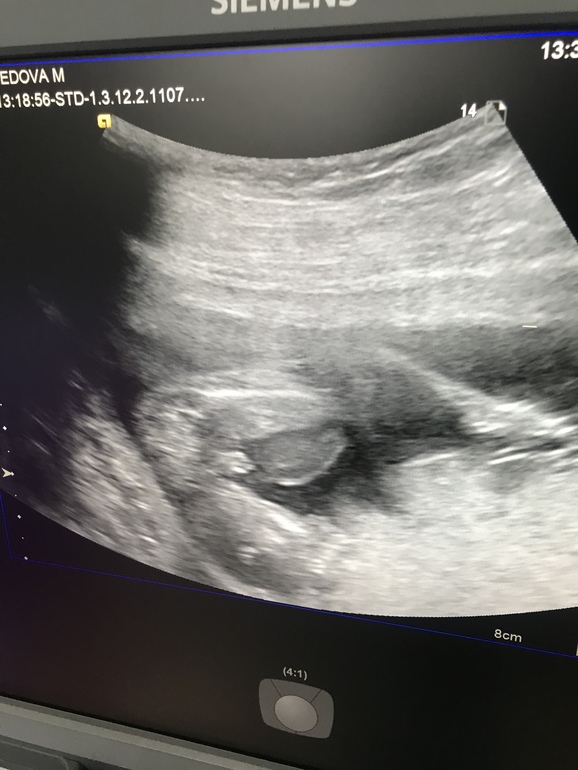

Пол малыша, часть вторая)))

С боку смотрела сказала девочка, снизу посмотрела говорит а нет на мальчика похож

Ну если так,то мальчик,вот причиндалы)🙈☺️☺️☺️ Растите здоровенькими...и судя по тому что малыш не пухляк пока-будете длинными(хотя подкожный жир может конечно ещё нарости)☺️☺️☺️☺️